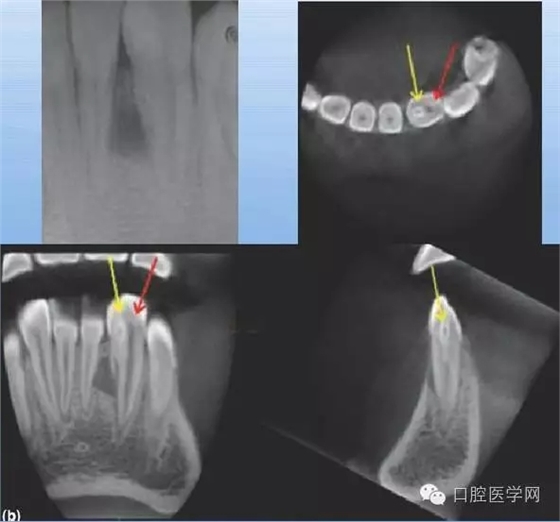

額外牙

X線表現(xiàn):最多見于上頜兩中切牙之間;圓錐形,根短小;拍攝X線片可確定額外牙的數(shù)目、位置、形態(tài)與鄰牙的關(guān)系。